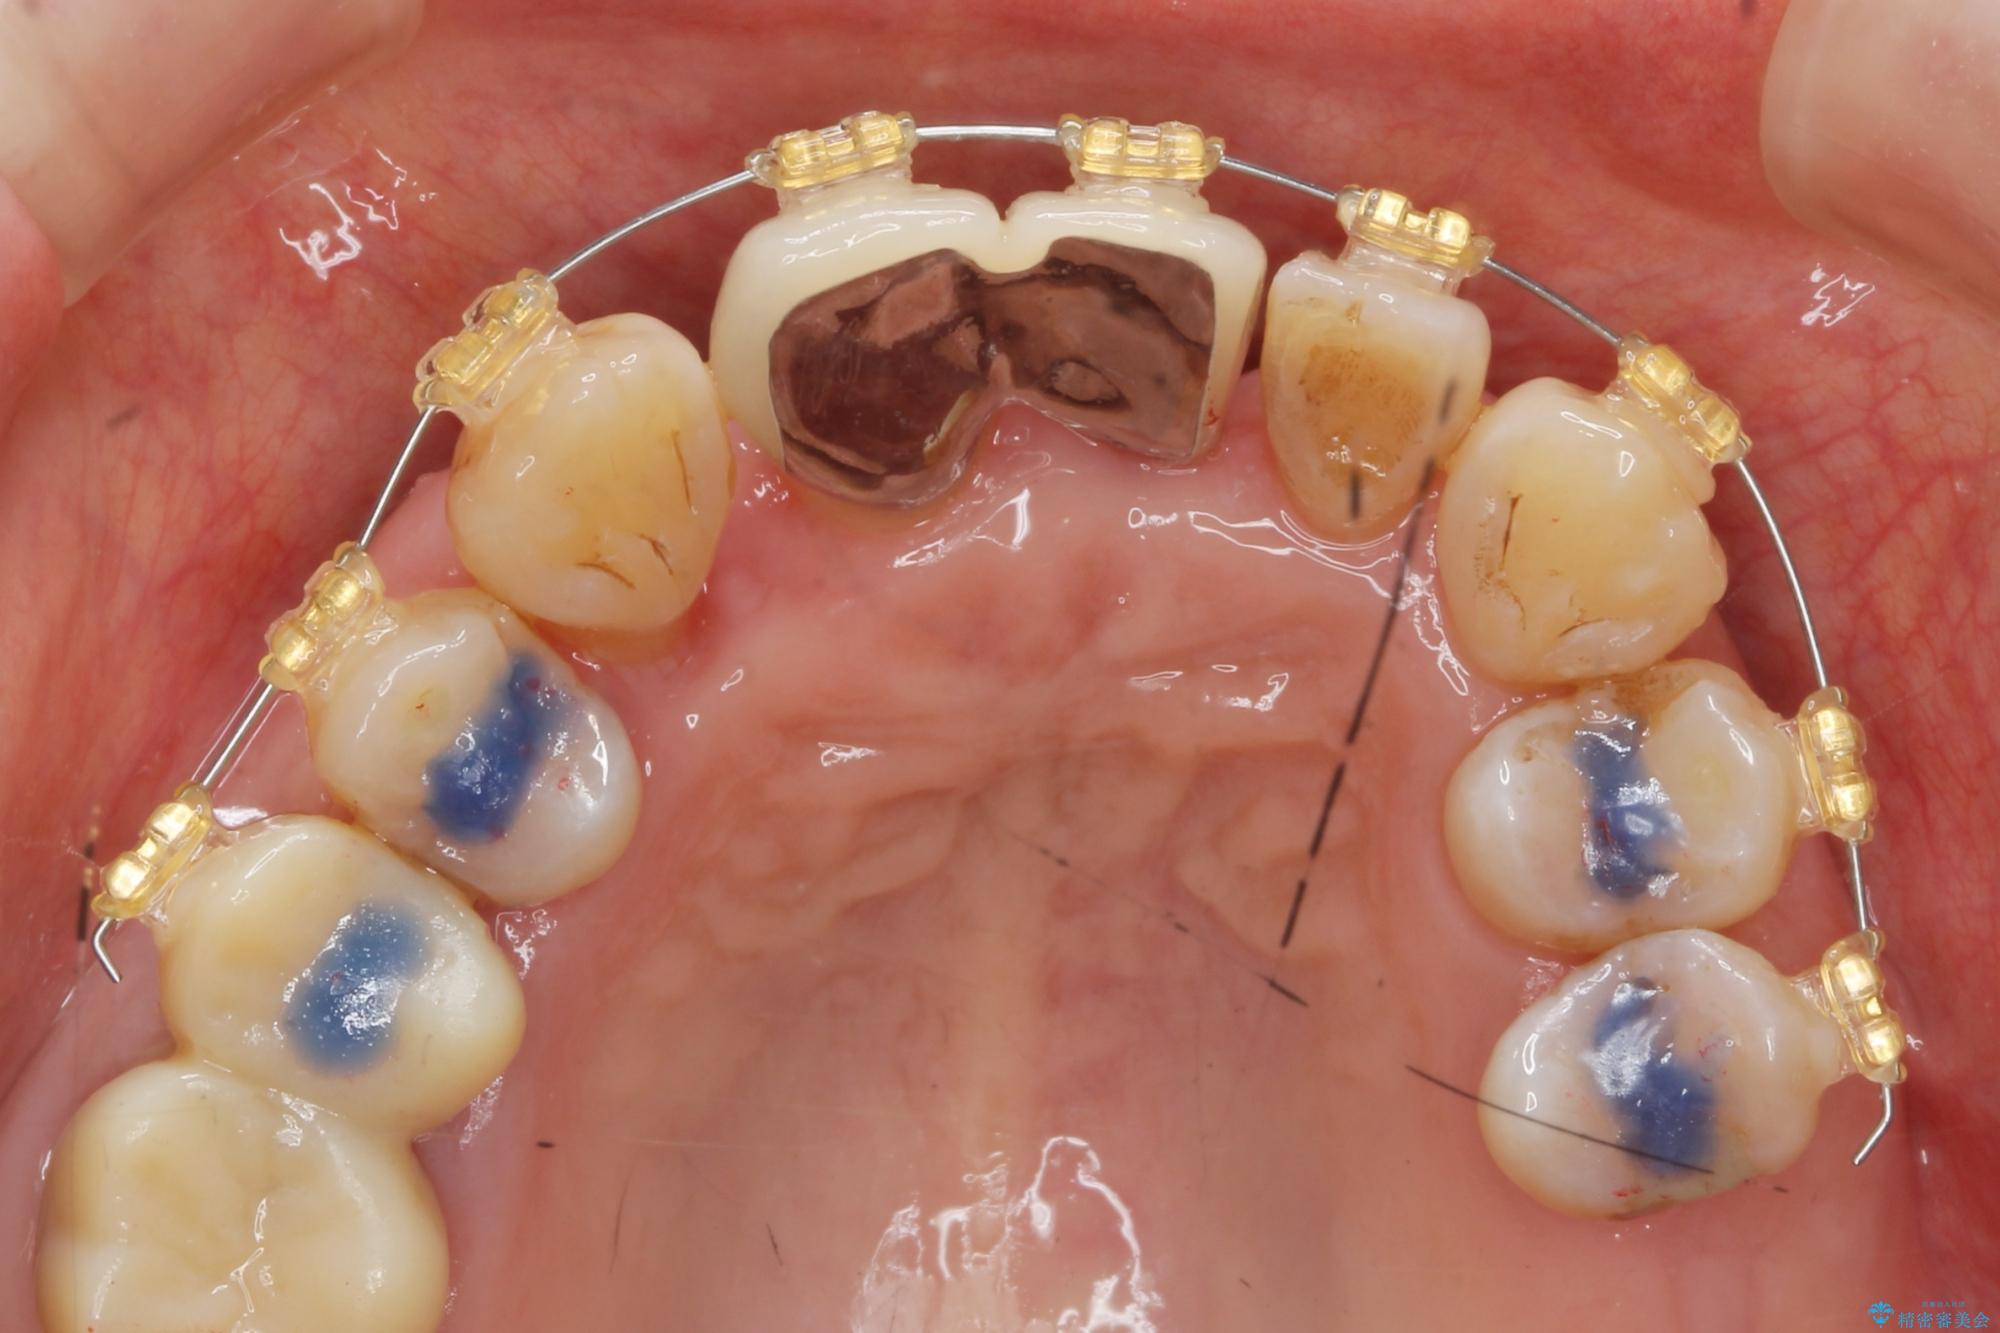

治療中

歯の総合的なマネージメントを行う包括的歯科治療の実践[ 歯周病・矯正・セラミック補綴 ] 治療中画像 歯の総合的なマネージメントを行う包括的歯科治療の実践[ 歯周病・矯正・セラミック補綴 ] 治療中画像 歯の総合的なマネージメントを行う包括的歯科治療の実践[ 歯周病・矯正・セラミック補綴 ] 治療中画像 歯の総合的なマネージメントを行う包括的歯科治療の実践[ 歯周病・矯正・セラミック補綴 ] 治療中画像 歯の総合的なマネージメントを行う包括的歯科治療の実践[ 歯周病・矯正・セラミック補綴 ] 治療中画像 歯の総合的なマネージメントを行う包括的歯科治療の実践[ 歯周病・矯正・セラミック補綴 ] 治療中画像 歯の総合的なマネージメントを行う包括的歯科治療の実践[ 歯周病・矯正・セラミック補綴 ] 治療中画像 歯の総合的なマネージメントを行う包括的歯科治療の実践[ 歯周病・矯正・セラミック補綴 ] 治療中画像 歯の総合的なマネージメントを行う包括的歯科治療の実践[ 歯周病・矯正・セラミック補綴 ] 治療中画像 歯の総合的なマネージメントを行う包括的歯科治療の実践[ 歯周病・矯正・セラミック補綴 ] 治療中画像 歯の総合的なマネージメントを行う包括的歯科治療の実践[ 歯周病・矯正・セラミック補綴 ] 治療中画像